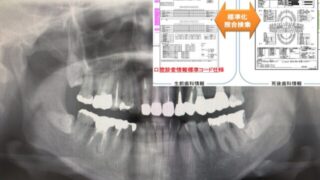

歯科関係者向け情報 パノラマエックス線画像AIによる「個体識別」「警察歯科」「災害時身元確認」への応用 「災害大国・日本」で、歯科が担う社会的役割の一つに身元確認(個体識別)があります。東日本大震災では、歯科所見と生前の歯科診療情報の照合が身元確認に有効であることが示されましたが、同時に「情報収集の困難さ」「標準化不足」「人的負担の大きさ」も... 2026.01.25 歯科関係者向け情報気になる歯科情報